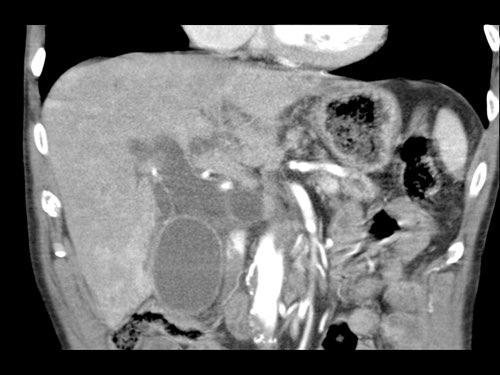

Ở những bệnh nhân dự kiến phẫu thuật tụy, điều quan trọng là cần đặc biệt chú ý tìm kiếm nguyên ủy bất thường của động mạch gan phải hoặc động mạch gan chung.

Các động mạch này xuất phát từ phía phải của động mạch mạc treo tràng trên (SMA) và đi qua vùng lân cận đầu tụy, làm tăng nguy cơ xâm lấn của khối u hoặc tổn thương do phẫu thuật.

Tần suất được ghi nhận của các bất thường đặc hiệu này lần lượt là 11-21% và 0,5-5%.

Các hình ảnh mặt phẳng đứng ngang của một bệnh nhân có khối u ở đầu tụy và động mạch gan phải phụ thêm.

Lưu ý sự áp sát của động mạch phụ thêm bởi khối u.